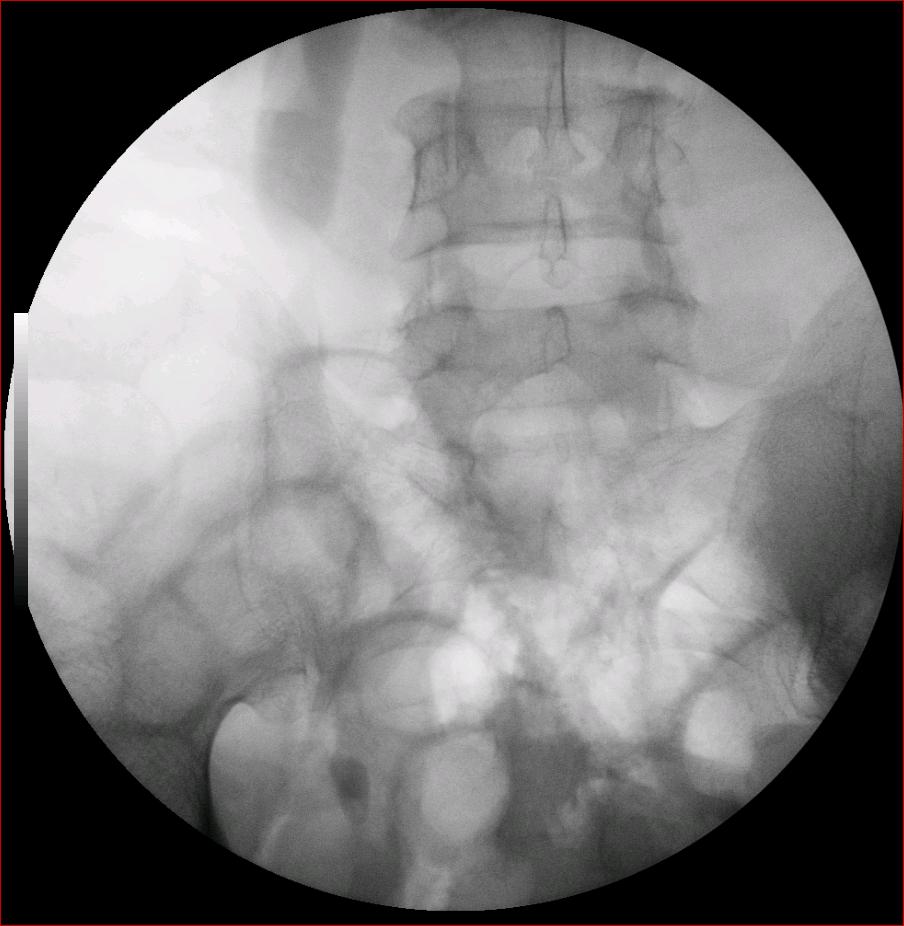

以下是引用luoxinjun在2008-2-18 15:54:00的发言:[br]右肾积水,右输尿管下端结石

以下是引用zhangxiangjun在2008-2-18 21:01:00的发言:[br]右输尿管盆段末端结石,继发其近端输尿管、右肾积水。

以下是引用hexue在2008-2-18 17:33:00的发言:[br]右输尿管下段结石并右肾及右输尿管积水扩张

以下是引用杀毒软件在2008-2-18 16:24:00的发言:[br]右输尿管下段结石,肾盂积水。